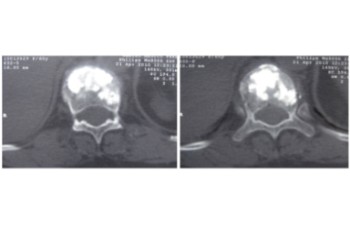

Resección (corpectomía) y reconstrucción vertebral de fracturas vertebrales complejas y conminutas

En los casos de las fracturas más graves, las fracturas conminutas y fracturas estallido, pueden conllevar que un fragmento del cuerpo vertebral se haya desplazado hacia el canal medular, provocando una compresión de las estructuras neurológicas (estenosis del canal medular).

En los casos en los que existe un compromiso neurológico se debe proceder a la resección parcial o total del cuerpo vertebral fracturado (corpectomía) y su posterior reconstrucción mediante una caja somática expandible. Se suele completar la reconstrucción mediante una artrodesis percutánea instrumentada y cementada de los niveles adyacentes a la fractura. La resección (corpectomía) permite extraer el fragmento de la vértebra que se encuentra en el canal medular y liberar las estructuras neurológicas afectadas. La reconstrucción mediante una caja somática permite descargar la carga del paciente sobre la fractura y quitar el dolor que ésta le provoca al paciente.

Caso clínico de una resección (corpectomía) y reconstrucción vertebral lumbar en una fractura estallido de nivel L4.